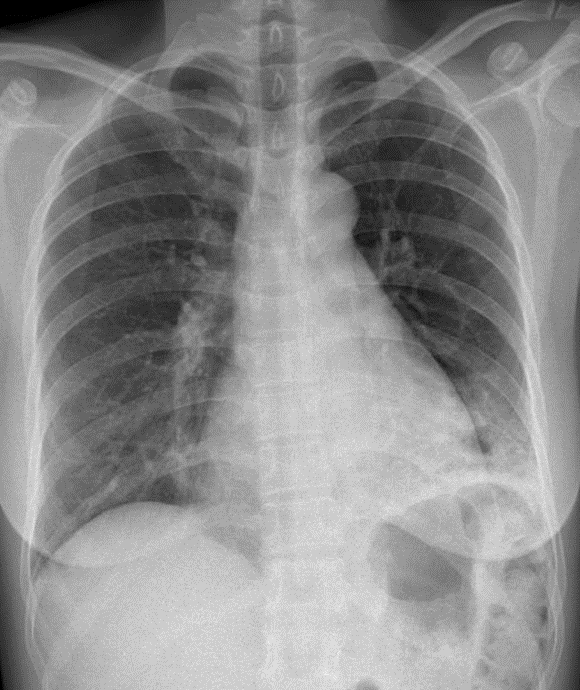

Hãy phân tích tình huống nữ 46 tuổi

1-Thâm nhiễm phế nang thùy dưới phổi (T) => Viêm phổi